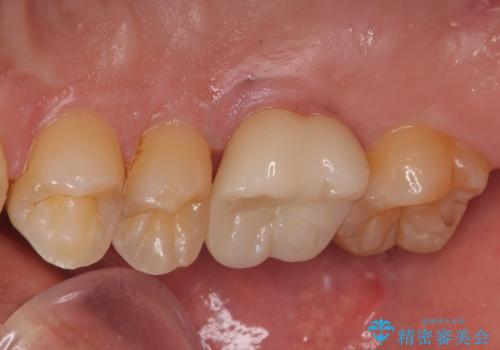

前から6番目の歯の頬側は個人差はありますが笑った時に見えるのでセラミックによる治療を行うと非常に審美的です。

見た目、機能面ともに満足していただけました。

噛み合わせが強いので今後はナイトガードを使ってもらいながらメンテナンスで通ってもらい経過を診ていく予定です。